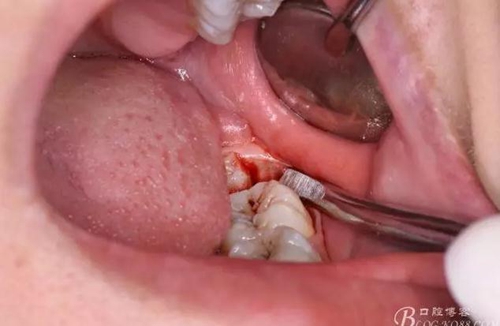

圖7.高速渦輪鉆分牙

圖8.先從頸部橫斷38

圖9.再把38牙冠近遠(yuǎn)中縱斷